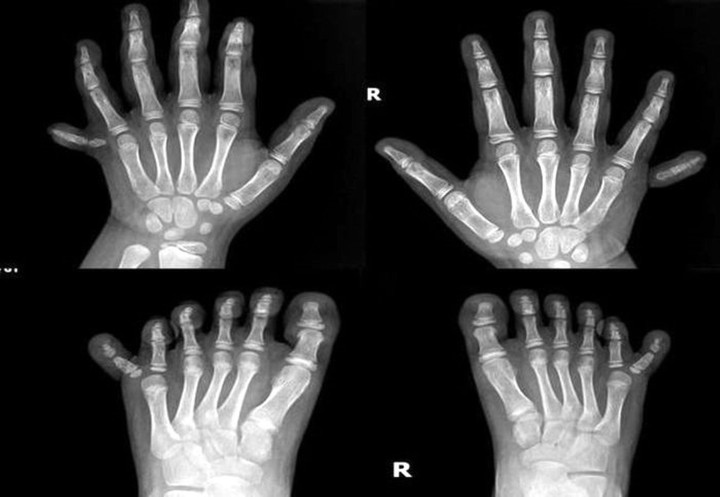

Hình ảnh chụp X-quang bàn tay và chân cháu T.L. (Ảnh: Bệnh viện cung cấp)

Mỗi bàn tay, bàn chân của T.L. có đến 6 ngón, tổng cộng bé có 12 ngón tay, 12 ngón chân. Việc dư thừa các ngón tay, chân khiến cho sinh hoạt của cháu bị cản trở, đặc biệt là khi lựa chọn giày, vận động, chạy nhảy.

Theo bác sĩ chuyên khoa I Huỳnh Đắc Anh, dị tật thừa ngón này gặp phải ở khoảng 2/1.000 trẻ sơ sinh, thường cần phải phẫu thuật để điều trị. Tuy nhiên, sự xuất hiện đồng thời của dị tật thừa ngón ở cả tứ chi cùng lúc là một trường hợp cực kỳ hiếm gặp, chỉ với một số ít trường hợp được báo cáo trên toàn thế giới.